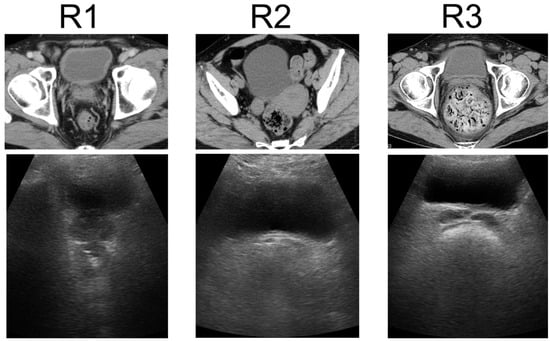

| R1 | 92 (68) | |

| R2 | 33 (25) | |

| R3 | 9 (7) | |

| R2 + R3 | 42 (31) | |

| Diagnosis concordance rate of R1, R2, and R3 (%) | 93 | |

| Diagnosis concordance rate of R1 and R2 + R3 (%) | 97 | |